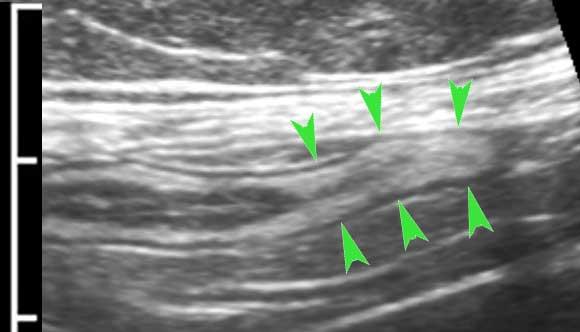

Đây là hình ảnh của hồi tràng tận cùng ở ba trẻ em và người trẻ tuổi khác nhau với các mảng Peyer lớn biểu hiện dưới dạng dày lớp niêm mạc sâu không đối xứng, giảm âm.

Với mỗi kháng nguyên mới, mô bạch huyết lại được tái hoạt hóa.

Ở bệnh nhân trẻ tuổi, cả hạch bạch huyết mạc treo ruột và các mảng Peyer đều lớn hơn nhiều so với người trưởng thành – kể cả về kích thước tuyệt đối.

Mô bạch huyết bị kích thích ở trẻ em không chỉ dẫn đến các mảng Peyer nổi bật ở hồi tràng đoạn cuối và các hạch bạch huyết mạc treo ruột phì đại (hình dưới bên trái), mà còn gây ra tình trạng dày lớp niêm mạc sâu của ruột thừa (hình dưới bên phải).

Lưu ý rằng các phần lồi ra –đôi khi giống polyp- (góc trên bên phải), có thể đóng vai trò là điểm dẫn đầu trong lồng ruột hồi-manh tràng điển hình ở trẻ nhỏ